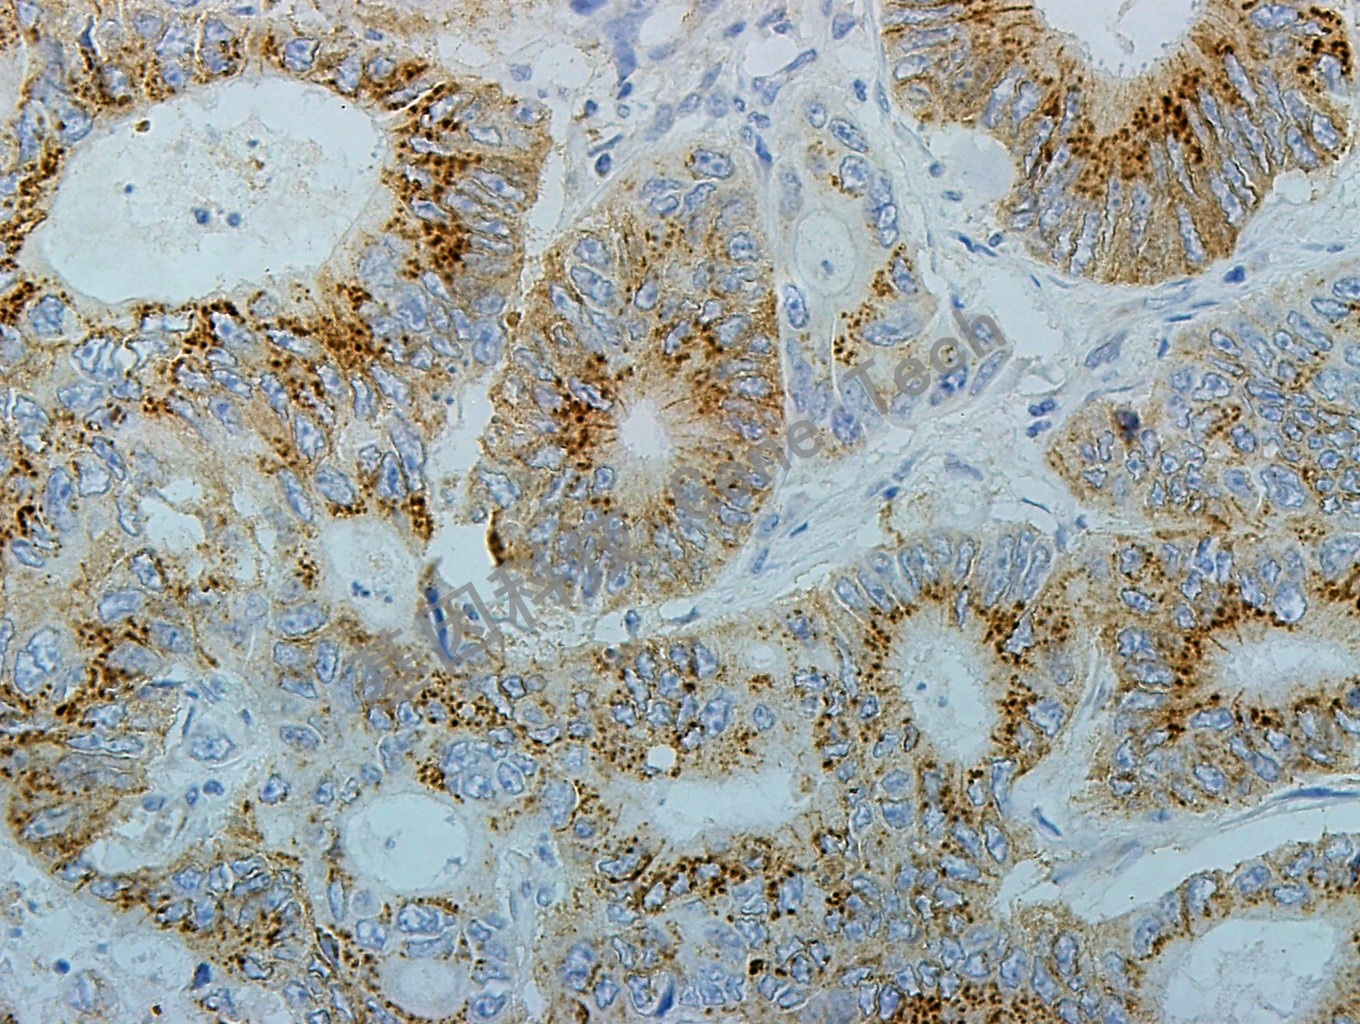

| 簡(jiǎn)介:Bak又稱Bcl-2-同源性抑制物,由211個(gè)氨基酸組成,是Bcl-2家族的同源蛋白參與凋亡控制。Bcl-2相關(guān)蛋白通過(guò)形成同源或異源二聚體形式相互作用,細(xì)胞對(duì)凋亡刺激的敏感性被認(rèn)為與這些Bcl-2家族蛋白之間的相對(duì)比例有關(guān)系。研究發(fā)現(xiàn)Bak能夠加速被剝奪生長(zhǎng)因子的粘膜下淋巴、神經(jīng)元及成纖維細(xì)胞系的凋亡。免疫組織化學(xué)染色顯示該蛋白位于胞漿內(nèi)呈斑點(diǎn)狀分布,其分布特點(diǎn)與Bcl-2家族其它蛋白一致,與其分布在胞內(nèi)的細(xì)胞器有關(guān)。 | ||

| 結(jié)腸癌石蠟切片,用 Bak(GT2229)染色,細(xì)胞漿陽(yáng)性,DAB 顯色。(40×) | ||